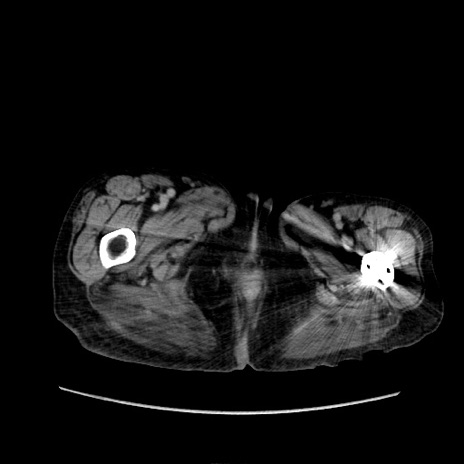

症例31(横断像)

【症例】80歳代 女性

【主訴】腹部膨満感

【現病歴】他院にて肝硬変にてフォロー中。1週間前から便秘、腹部膨満感、臍部腫瘤あり受診となる。

【既往歴】肝硬変

【身体所見】腹部膨隆あり、皮膚変化なし、疼痛なし。

【データ】WBC 4600、CRP 0.25